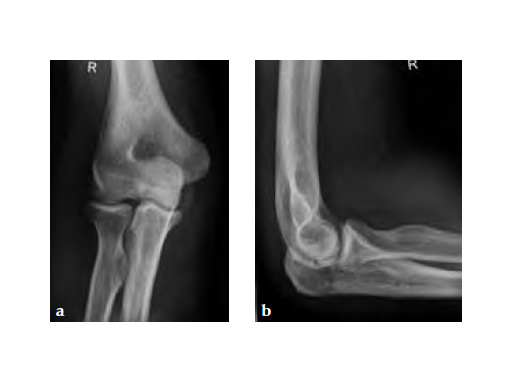

30-year-old male.

Fig 1ab Preoperative AP and lateral x-rays.